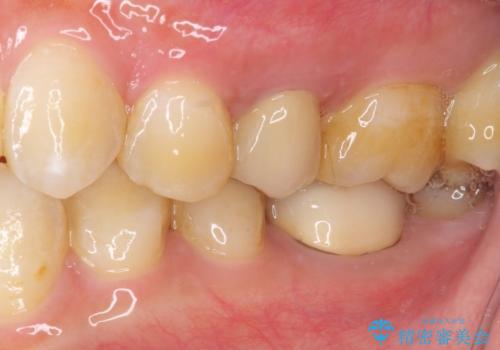

- 冷たいものがしみるとのことで来院された患者様です。

診査を行った結果、第一小臼歯にある樹脂の詰め物(コンポジットレジン)と歯の境目が痛みの原因であることが分かりました。

また、隣接する第二小臼歯も虫歯になっていることも分かったため、2歯を同時に治療するにしました。

下顎の目立つ位置であるため、セラミックインレーによる修復治療を行うこととしました。

精密に型取りを行ったセラミックインレーを装着したことで、治療後にはしみたり痛んだりという症状は治まりました。